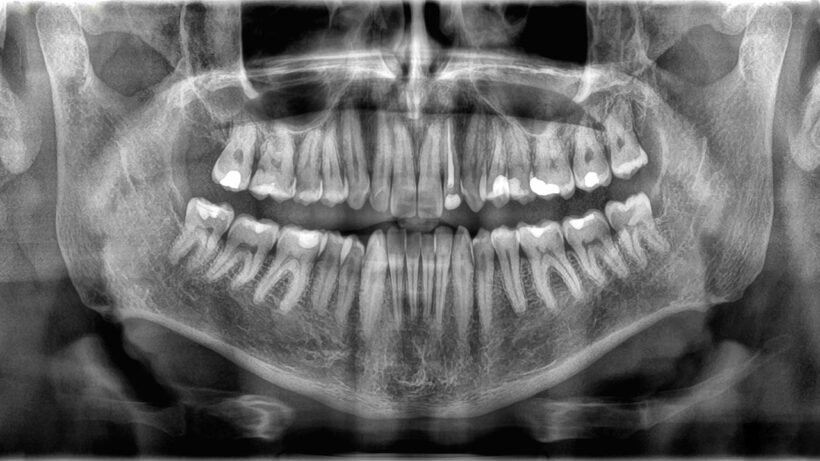

Поскольку кости и зубы выполняют разные задачи, они и устроены по-разному. Внешняя структура зуба — это эмаль, тонкий слой минерализованной ткани. Эмаль — самое твердое вещество в организме, и свою прочность она получает благодаря плотно упакованным кристаллам из соединения кальция и фосфата.

Под эмалью лежит дентин — тип минерализованной ткани, который немного мягче эмали, но все же очень тверд. Дентин составляет основную часть структуры зуба и содержит микроскопические канальцы, в которых находятся кровеносные сосуды и нервные окончания. В центре зуба находится пульпа — желеобразное вещество, содержащее еще больше сосудов, которые питают зуб, и нервов, которые отвечают за его чувствительность.

Структура костей, напротив, выглядит совершенно иначе. Кости покрыты очень тонкой, но прочной внешней оболочкой — надкостницей, в которой находятся кровеносные сосуды и нервы, essential для роста и заживления ткани. Следующий слой состоит из прочной компактной костной ткани. Внутри кость содержит губчатую ткань — похожее на губку вещество с мелкими отверстиями, в которых находится костный мозг, производящий новые кровяные клетки.